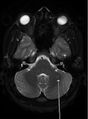

- MRI

- Multiple lesions in supratentorial white matter, paraventricular area, spinal cord